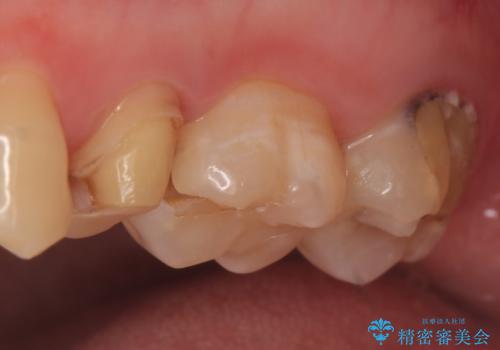

- 左上の歯が痛くてものが咬めないといらっしゃった方の症例です。

左上6は自発痛および持続痛を認めたため根管治療後、オールセラミッククラウンによる補綴を行いました。

左上7は冷水痛のみだったため、慎重に虫歯の除去を行い症状がないことを確認後、オールセラミッククラウンによる補綴を行いました。

左上5は再根管治療後、オールセラミッククラウンによる補綴を行いました。